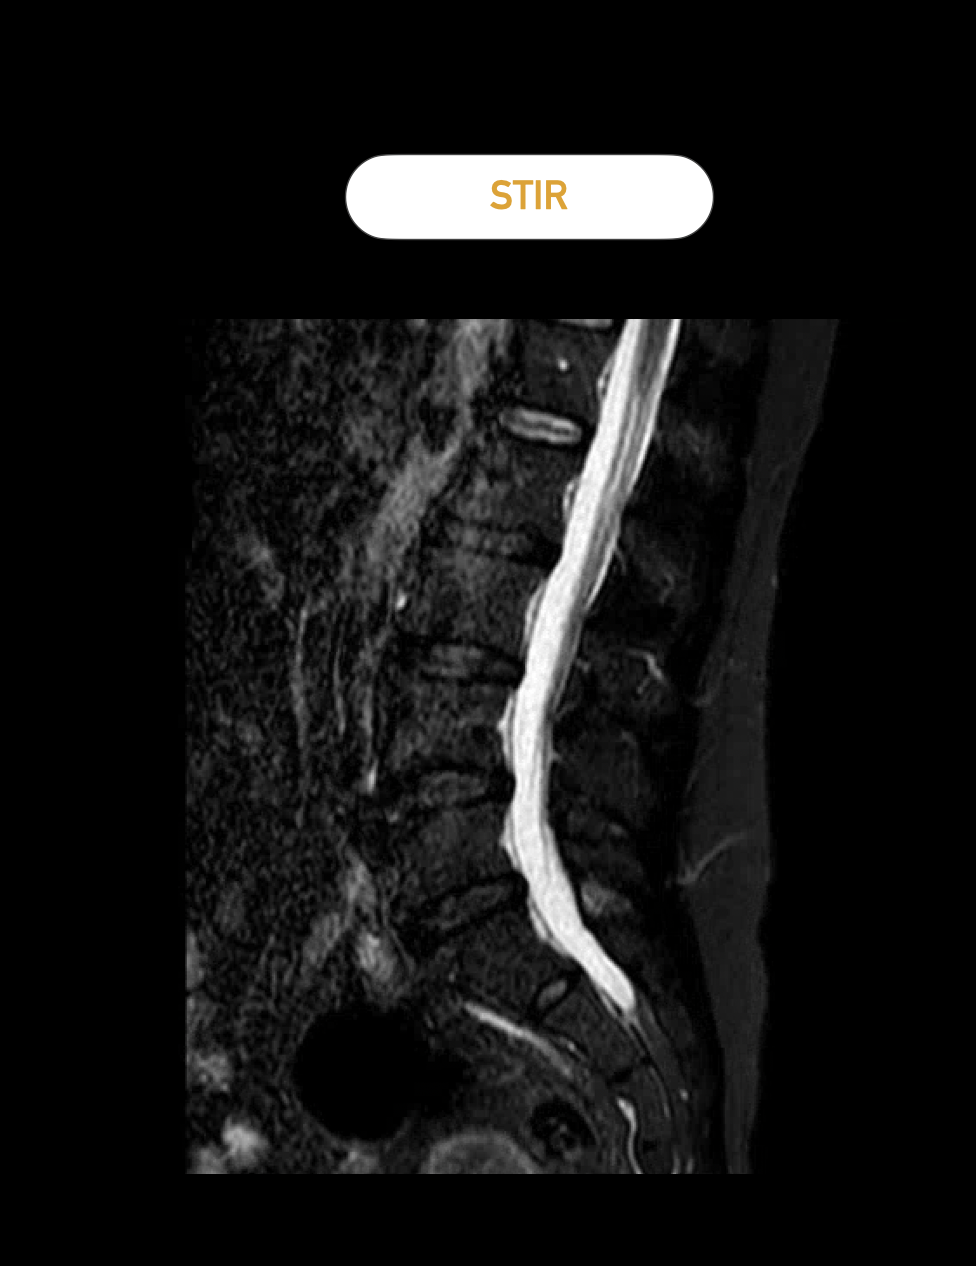

Die STIR-Sequenz ist ebenfalls eine T2-Wichtung, zeigt aber besonders gut Knochenödeme. Bei der Frage nach Wirbelkörperfrakturen ist dies besonders hilfreich.